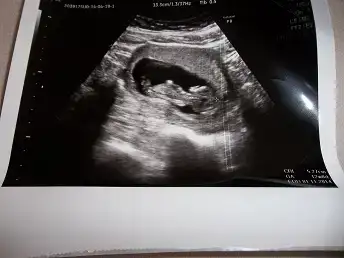

$100_0199.webp Burda 12. haftamızı bitiriyoruz doktoromuz cinsiyetini görmüs ama heyecanlı olması için haftaya söyleyecek.öğrenince yazarım.

12+2 olduk bu gün teyzesi doktorumuz görmüs ama haftaya söyleyecekmis heyecanlı olsun diye :) ben ölüyorum meraktan haberi yok :))) siz tahminlerinizi yapın c.tesi kontrol sonucunu yazcam zaten.:emir_bebek: